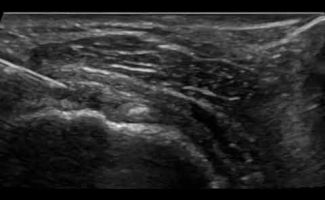

- Έγχυση Kορτικοστεροειδούς στο περίβλημα (έλυτρο) του τένοντα: Η έγχυση με κορτιζόνη καταστέλλει τη φλεγμονή γύρω από τον τένοντα, οδηγώντας στην άμεση ανακούφιση του ασθενούς από το πόνο και το πρήξιμο. Η στοχευμένη διενέργεια αυτών των ενέσεων είναι πολύ σημαντική: η έγχυση πρέπει να γίνει στο περίβλημα του τένοντα, και όχι στο εσωτερικό του, καθώς η έγχυση στο εσωτερικό μπορεί να προκαλέσει φθορά και ρήξη του τένοντα. Τα μηχανήματα υπερήχων μας παρέχουν το απαραίτητο επίπεδο ακρίβειας καθώς καθοδηγούμε τη βελόνα με ταυτόχρονη απεικόνιση και διοχετεύουμε το φάρμακο εκεί ακριβώς που χρειάζεται. Επομένως, το επίπεδο ακρίβειας που εγγυάται η απεικόνιση σημαίνει ότι υπάρχει υψηλή πιθανότητα η θεραπεία να είναι ακόμα πιο αποτελεσματική.

- Απόλυτη Ακρίβεια: Οι υπέρηχοι επιτρέπουν στους Ιατρούς-Ακτινολόγους να εντοπίζουν με ακρίβεια τον φλεγμονώδη τένοντα και να οπτικοποιούν τη θέση της βελόνας κατά τη διάρκεια της ενέσεως. Αυτή η στοχευμένη προσέγγιση εξασφαλίζει την τοποθέτηση της ένεσης με ακρίβεια στην περιοχή που πλήττεται, βελτιώνοντας την αποτελεσματικότητά της.

- Ασφαλείς: Σε σύγκριση με την ενέσιμη θεραπεία χωρίς υπερηχογραφική καθοδήγηση (τυφλή ένεση), η εικόνα πραγματικού χρόνου επιτρέπει στον ιατρό να διεξάγει την ένεση ακριβώς στο σημείο που χρειάζεται, αποφεύγοντας επικίνδυνες περιοχές όπως τα νεύρα και τα αγγεία.